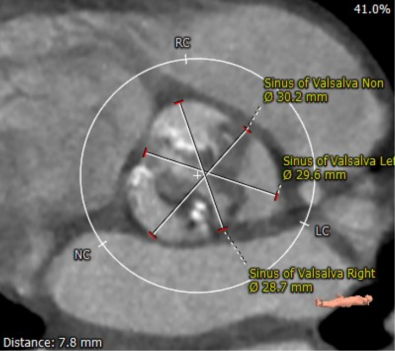

患者男性,70岁,重度钙化型主动脉瓣狭窄,STS评分8.6%,常规外科手术高风险。术前心脏超声提示主动脉瓣严重增厚钙化,峰值流速5.4m/s,平均跨瓣压差82mmHg。CT评估结果显示主动脉瓣重度钙化,瓣环平均直径23.9mm,瓣环面积448.4mm²。左冠脉开口高度8.5mm,右冠脉开口高度12.2mm。该患者左、右冠状动脉开口高度低,左冠瓣叶较长伴钙化,且瓦氏窦较小,窦管交界处高度低,冠状动脉阻塞风险高,手术操作复杂。

主动脉瓣瓣环

瓦氏窦直径